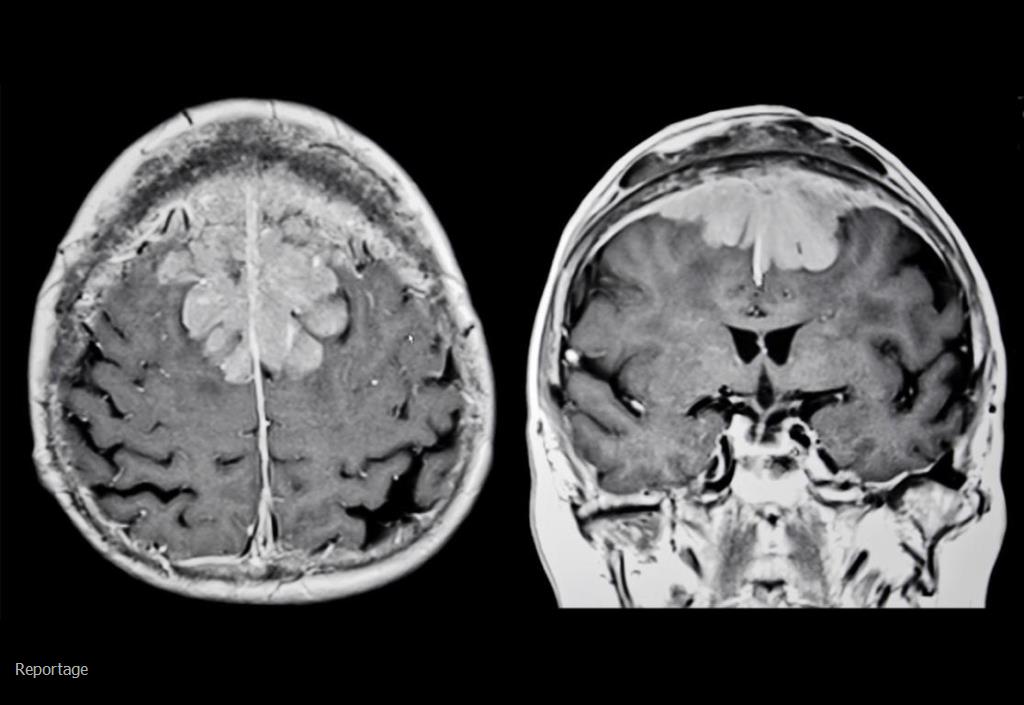

تومور مغزی چیست؟

تومور مغزی رشد سلول های غیر طبیعی در مغز است. آناتومی مغز بسیار پیچیده است و بخش‌های مختلفی مسئول عملکردهای مختلف سیستم عصبی هستند. تومورهای مغزی می توانند در هر قسمت از مغز یا جمجمه از جمله پوشش محافظ آن، قسمت زیرین مغز (پایه جمجمه)، ساقه مغز، سینوس ها و حفره بینی و بسیاری از نواحی دیگر ایجاد شوند. بیش از 120 نوع مختلف تومور وجود دارد که بسته به بافتی که از آن منشأ می گیرند، می توانند در مغز ایجاد شوند.

تومورهای مغزی خطرناک هستند زیرا می توانند بر قسمت های سالم مغز فشار وارد کنند یا به آن نواحی گسترش یابند. برخی از تومورهای مغزی نیز می توانند سرطانی شوند. اگر جریان مایع در اطراف مغز را مسدود کنند، می توانند مشکلاتی ایجاد کنند که می تواند منجر به افزایش فشار داخل جمجمه شود. برخی از انواع تومورها می توانند از طریق مایع نخاعی به مناطق دوردست مغز یا ستون فقرات پخش شوند.